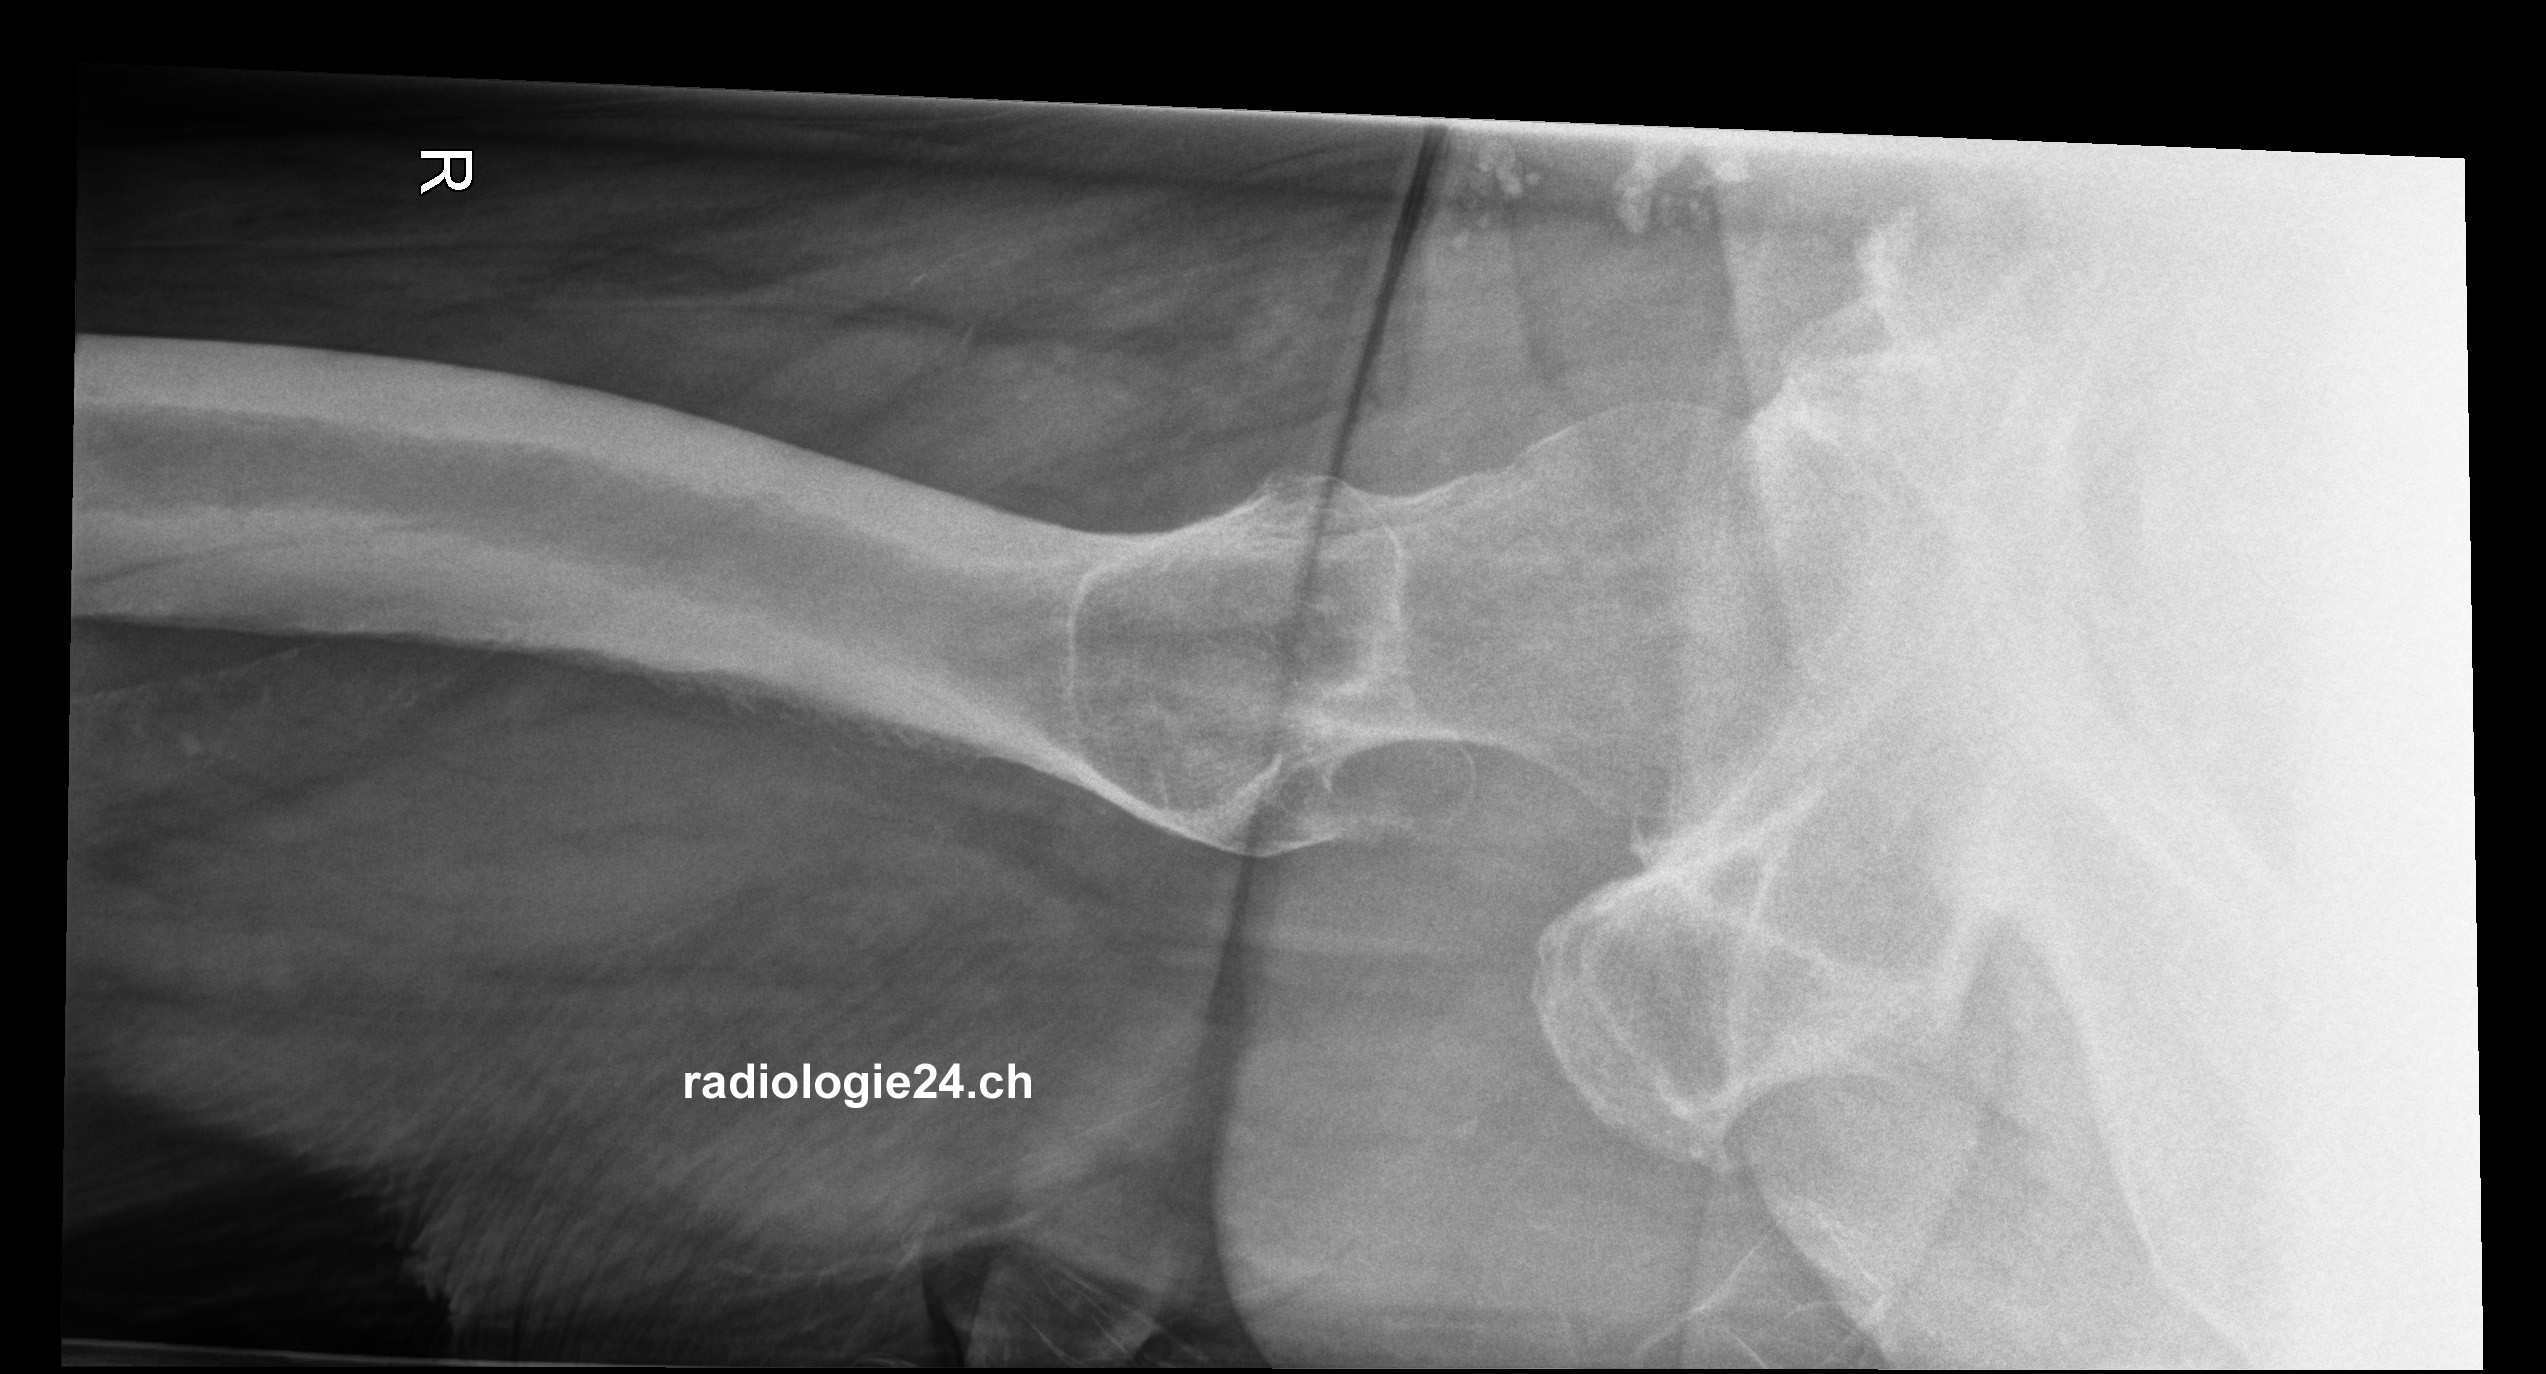

Röntgenfall des Monats August 2017 mit Auflösung

75 jähriger Patient therapierefraktäre Becken-/Hüftschmerzen rechts Diagnose/weitere radiologische Diagnostik?